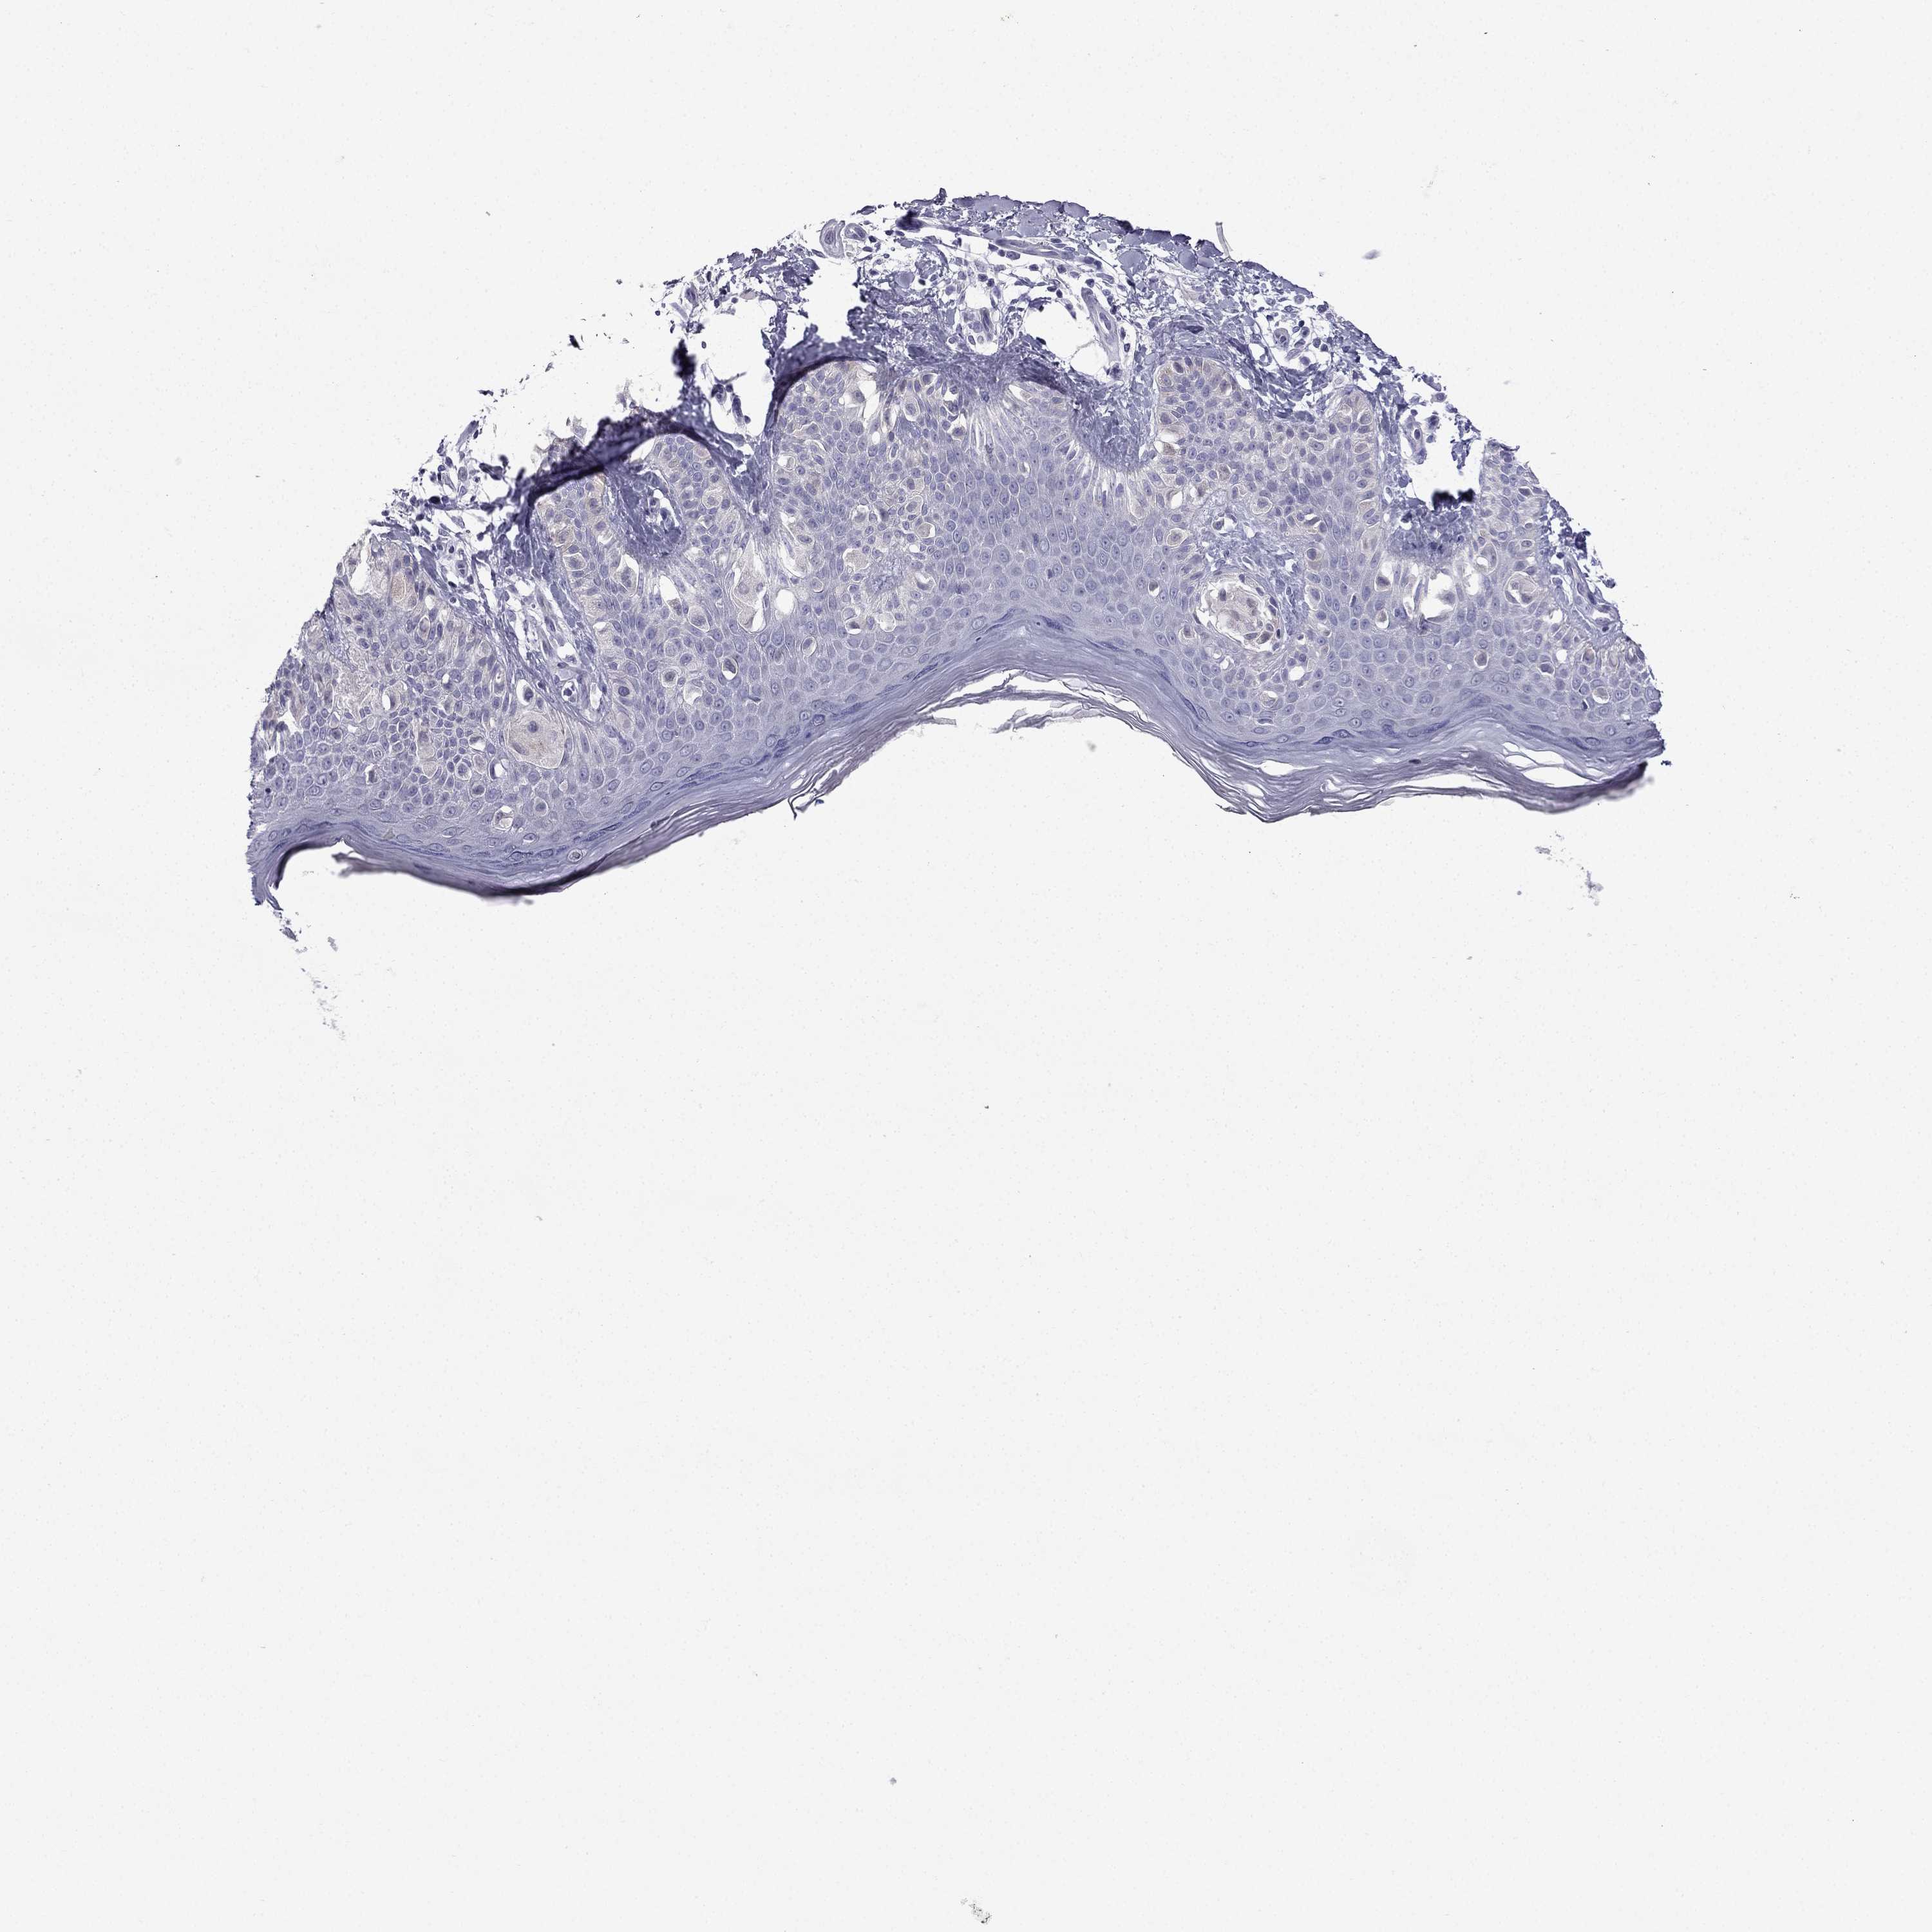

MELANOMA - Protein expressioni

A mouse-over function shows sample information and annotation data. Click on an image to view it in a full screen mode. Samples can be filtered based on level of antibody staining by selecting one or several of the following categories: high, medium, low and not detected. The assay and annotation is described here.

Note that samples used for immunohistochemistry by the Human Protein Atlas do not correspond to samples in the TCGA dataset.

Antibody stainingi

Antibody staining in the annotated cell types in the current human tissue is reported as not detected, low, medium, or high, based on conventional immunohistochemistry profiling in selected tissues. This score is based on the combination of the staining intensity and fraction of stained cells.

Each image is clickable and will lead to virtual microscopy that enables deeper exploration of all samples and also displays staining intensity scores, fraction scores and subcellular localization as well as patient and tissue information for each sample.

Antibody HPA066142

Staining

High

Medium

Low

Not detected

Intensity

Strong

Moderate

Weak

Negative

Quantity

>75%

75%-25%

<25%

None

Location

Nuclear

Cytoplasmic/membranous

Cytoplasmic/membranous,nuclear

Malignant melanoma, NOS

Malignant melanoma, Metastatic site